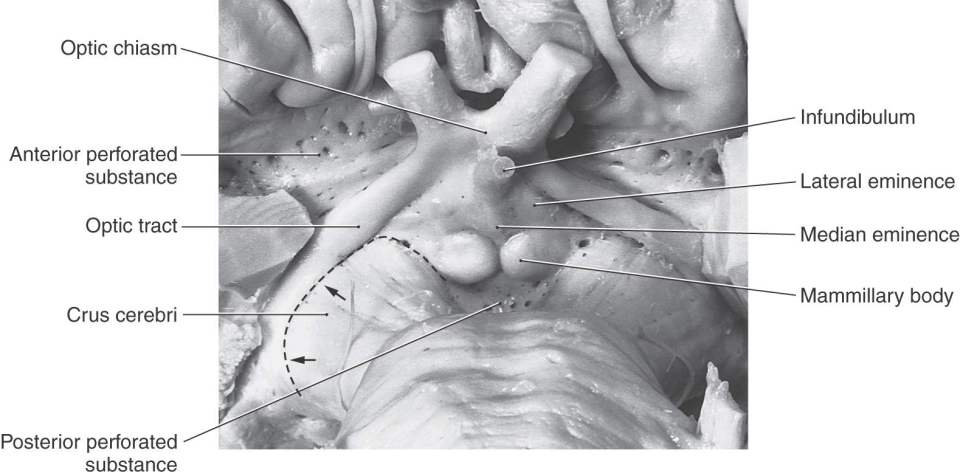

The junction between the diencephalon and midbrain lies along a line extending from the posterior commissure to the caudal edge of the mammillary body on the medial aspect of the hemisphere (Fig. 15-4). On the surface of the hemisphere, this interface is represented by a line starting at the caudal aspect of the mammillary body, extending anterolaterally over the edge of the crus cerebri, and following the caudal edge of the optic tract (Fig. 15-5). The boundary between the diencephalon and surrounding telencephalon is less distinct and is represented laterally by the internal capsule and rostrally by the interventricular foramen, lamina terminalis, and optic chiasm (Fig. 15-4).

Figure 15-5. Anterior (ventral) view of the hemisphere emphasizing diencephalic structures visible on the surface and showing the diencephalic-mesencephalic interface as represented by the caudal edge of the optic tract (arrows).

All four diencephalic subdivisions can be approximated in a midsagittal section of the forebrain (Figs. 15-4 and 15-6). The dorsal thalamus is located superior to the hypothalamic sulcus and extends from the interventricular foramen caudally to the level of the splenium of the corpus callosum. The hypothalamus lies inferior to the hypothalamic sulcus and is bordered rostrally by the lamina terminalis and caudally by a line that extends from the posterior aspect of the mammillary body superiorly to intersect with the hypothalamic sulcus. The only diencephalic structures visible on the inferior surface of the hemisphere are those related to the hypothalamus, including the optic chiasm, infundibulum, medial and lateral eminences, and mammillary bodies (Fig. 15-5). The ventral thalamus (subthalamus) does not border on the ventricle; rather, it occupies a position caudal to the hypothalamus, rostral to the diencephalon-midbrain junction, and lateral to the midline (Figs. 15-4 and 15-7B). Epithalamic structures are located posteriorly and caudally, in close apposition to the posterior commissure, and include the pineal gland, the habenular nuclei, and the main afferent bundle of these nuclei, the stria medullaris thalami.